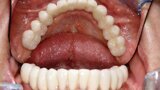

Natychmiastowa implantacja i zaopatrzenie protetyczne pacjentów z zaawansowaną chorobą przyzębia